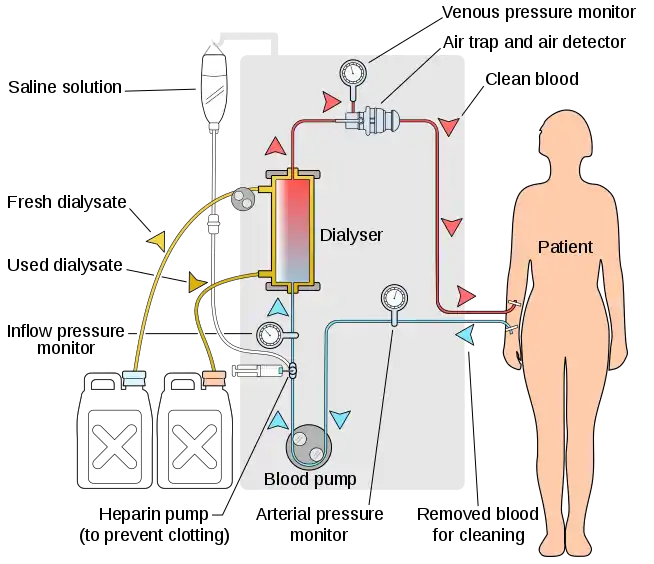

The principle of hemodialysis is the same as other methods of dialysis; it involves diffusion of solutes across a semipermeable membrane. Hemodialysis utilizes counter current flow, where the dialysate is flowing in the opposite direction to blood flow in the extracorporeal circuit. Counter-current flow maintains the concentration gradient across the membrane at a maximum and increases the efficiency of the dialysis.

Fluid removal (ultrafiltration) is achieved by altering the hydrostatic pressure of the dialysate compartment, causing free water and some dissolved solutes to move across the membrane along a created pressure gradient.

Equipment

The hemodialysis machine pumps the patient's blood and the dialysate through the dialyzer. The newest dialysis machines on the market are highly computerized and continuously monitor an array of safety-critical parameters, including blood and dialysate flow rates; dialysis solution conductivity, temperature, and pH; and analysis of the dialysate for evidence of blood leakage or presence of air. Any reading that is out of normal range triggers an audible alarm to alert the patient-care technician who is monitoring the patient. Manufacturers of dialysis machines include companies such as Nipro, Fresenius, Gambro, Baxter, B. Braun, NxStage and Bellco.